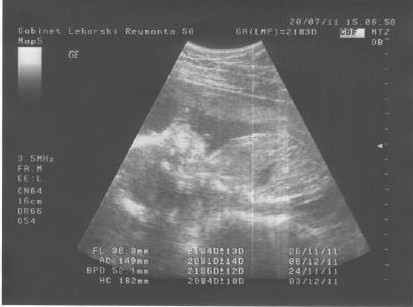

Aga7602, gratuluję dziewczynki..a tą miedniczką nerkową się nie łam..będzie dobrze!!!Mojej koleżanki córa (2 dni młodsza od mojej) miała podobnie, ale się jej wyrównało do miesiącaWczoraj byłam na usg połowkowym, ale nie mialam sie nawet siły odezwac do Was jeszcze wczoraj. Na 99% DZIEWCZYNKA.

Lekarz mi zrobił mnostwo pomiarów wszystkie oprocz jednego są dobre, od wczoraj zamartwiam sie tym jednm pomiarem, przeryczałam całą noc:-szok:- moja dziewczynka ma powiekszoną jedna miedniczke nerkową-wg niego moze to nic nie być ale do kontrolnego usg mam sie zgłosic za 2 tygodnie, a moze byc cos powazniejszego wiem juz co nie chce nawet tego pisać jestem zdruzgotana taka wiedzą.

Obecnie siedze i rycze nie umiem sie powstrzymać. Na wszelki wypadek zapisalam sie na za tydzien do znanego specjalisty diagnosty na konsultacje wyniku.

Kurde boje sie nieprzecietnie i niestety juz chyba do konca ciazy tak bedzie,:-( bo nikt mi nie zagwarantuje co bedzie po urodzeniu

Aga, niestety..najwyżej ją dopytam i Ci potem napiszę..Maxwell-czy moze wiesz jakie wymiary miedniczek miala coreczka twojej kolezanki?